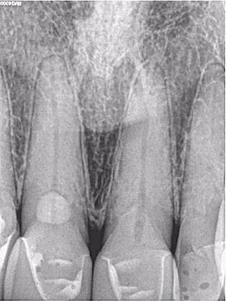

Mẹ tôi có tiền sử chấn thương khi đang chơi tennis với bố vài năm trước đây. Trước đó khi khám ở bác sĩ tổng quát, phim cận chóp hàm dưới gợi ý phải điều trị tủy, bà đến chỗ tôi ngay lập tức. Chất lượng phim cận chóp của chỗ bác sĩ trước không giống của mình, do đó tôi chụp lại một phim khác (Hình 17). Không chỉ thấy tổn thương nội tiêu nhỏ ở răng 46 mà còn tổn thương tiêu mở rộng răng 31 và 41 ban đầu khiến tôi nghĩ răng này không còn hy vọng gì và phải nhổ đi làm implant.

Hình 17: Ảnh XQ trước điều trị

Tuy nhiên sau khi chụp 3D, tôi đã có thể thấy mức độ tiêu xương ở lát cắt ngang, đứng dọc, đứng ngang; điều may mắn là nó không vượt ra khỏi phạm vi răng (hình 18 và 19).

Tôi quyết định theo dõi răng 46 và tiến hành điều trị răng 31, 41 bằng Ca(OH)2 (hình 20). 3 tuần sau hẹn bà tới trám bít ống tủy (hình 21). Bà quay lại để tái khám sau 1 năm vào mùa hè 2017. Kết quả điều trị coi như đã thành công, không thấy tiêu xương thêm (Hình 22). Hơn thế, răng 46 không thay đổi tình trạng tiêu. Có phim CBCT giúp theo dõi sự thay đổi về kích thước và mức độ tiêu xương trên răng bệnh nhân qua thời gian. Ngoài ra, CBCT cũng cho biết khi nào không nên điều trị, tôi đã tự tin chỉ cần theo dõi răng 46 từ đó hạn chế điều trị không cần thiết cho chính mẹ mình.